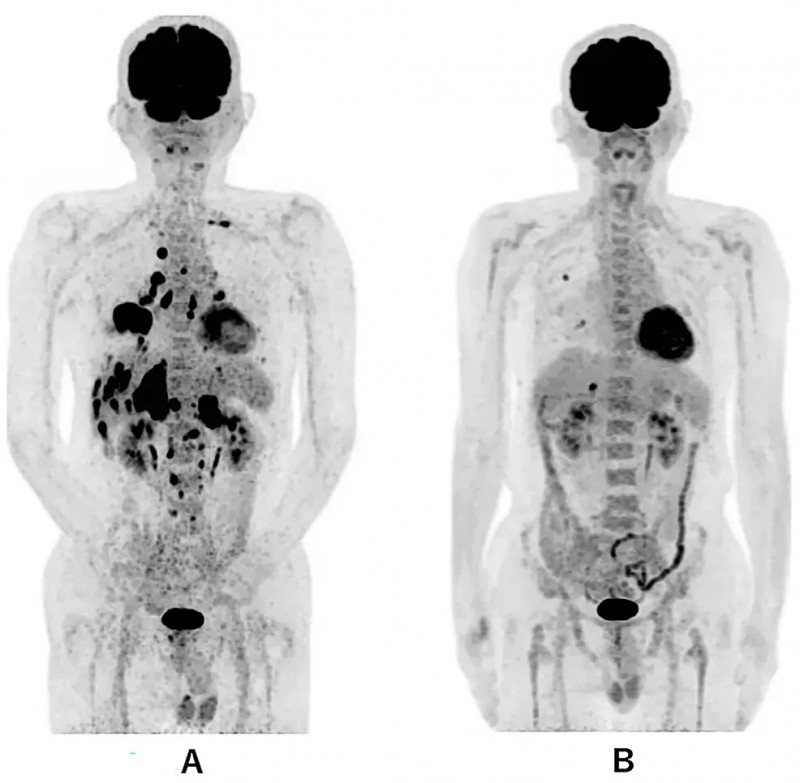

WT1-DC联合化疗为晚期肺癌患者续命,病灶近乎消失+PFS超1.5年

《Cureus》杂志近期报道了一例肺癌治疗突破性案例:一名69岁男性患者确诊为右肺中叶IV期鳞状细胞癌,确诊时已发生多发性骨、肝及双侧肾上腺转移,且因身体状况无法耐受手术与放疗。此后患者采用WT1树突状细胞疫苗(WT1-DC)+卡铂AUC6+紫杉醇的化疗方案联合治疗。

治疗成效十分显著:患者无进展生存期(PFS)超577天,期间体能状态良好,可正常生活。其癌胚抗原(CEA)曾一度持续上升,后续经雷莫芦单抗+多西他赛联合治疗后降至5.9。影像检查显示,治疗前PET-CT提示全身广泛转移;治疗第479天复查时,仅右肺(直径1.0cm)及肝脏(直径1.7cm)残留两处转移灶,其余病灶均明显改善。此外,胸部CT结果显示,治疗第114天肺部原发病灶已近乎消失;第213天虽出现局部复发,但第338天时,原发及复发病灶均显著缩小。

▼该患者WT1-DC治疗前后全身PET-CT对比

▲图源“Cureus”,版权归原作者所有,如无意中侵犯了知识产权,请联系我们删除

▼该患者WT1-DC治疗前后胸部CT图像对比